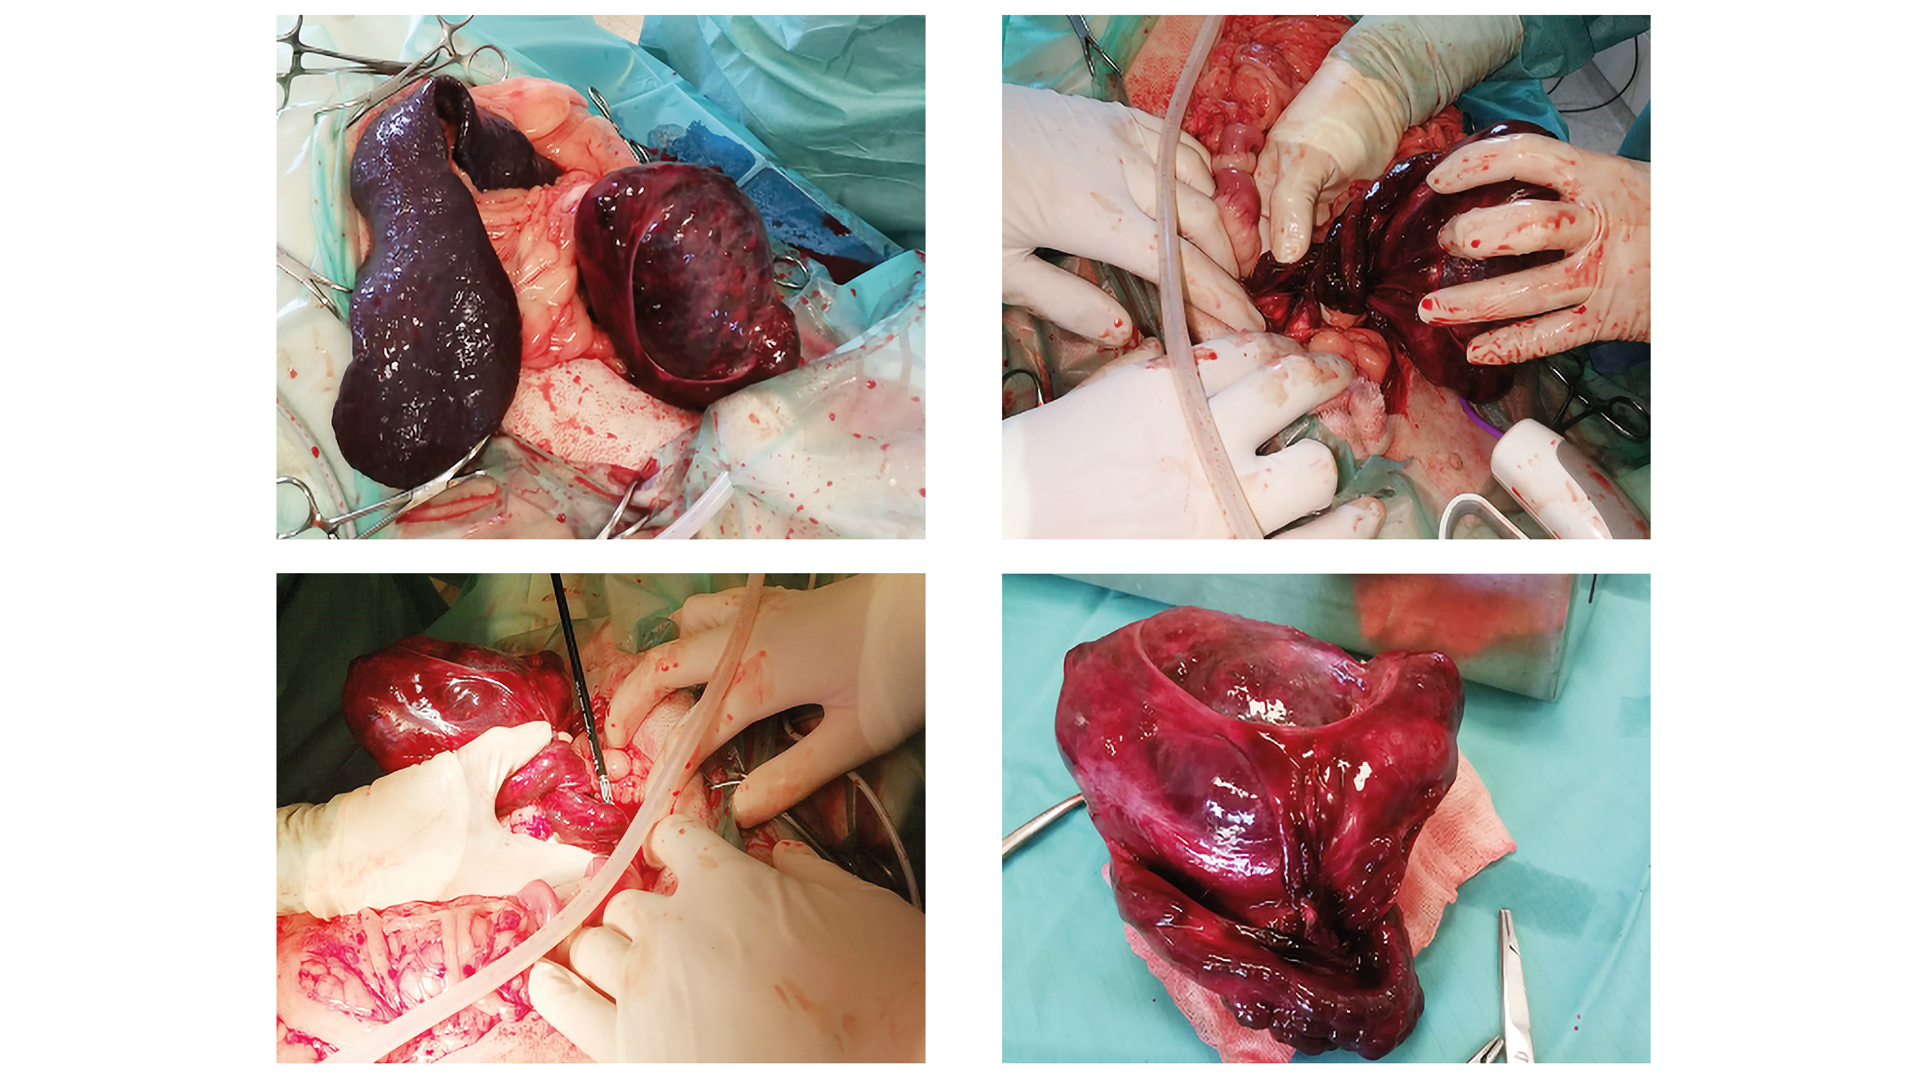

Während der OP-Vorbereitung wurde der Kryptorchismus des Rüden festgestellt und zum ersten Mal die Hypothese eines intraabdominalen Hodentumors gestellt.

Nach Eröffnung in der Linea alba wurde die blutige, abdominale Flüssigkeit abgesaugt. Die zuvor palpierte Umfangsvermehrung lag kindskopfgroß, dunkelrot bis dunkellila verfärbt, rechts kraniolateral der Harnblase. Sie entpuppte sich als torquierter, kryptorcher Hoden. Der Samenstrang war vier Zentimeter proximal des Hodens im Uhrzeigersinn um mehr als 360 Grad gedreht (Abb. 5 oben). Der Hoden war hämorrhagisch infarziert und hochgradig vergrößert. Dieser wurde – ohne ihn vorher auszudrehen – Schritt für Schritt mit dem Liga Sure proximal der Torsionsstelle abgesetzt (Abb. 5 unten). Eine Identifikation des Harnleiters bzw. dessen Beteiligung an der Torsion war intraoperativ nicht nachvollziehbar. Die Bauchhöhle wurde mit körperwarmer Ringerlösung gespült. Nach genauer Kontrolle auf Blutungen wurde das Abdomen in drei Schichten verschlossen. Der Hoden -wurde zur pathologischen Untersuchung eingesandt.